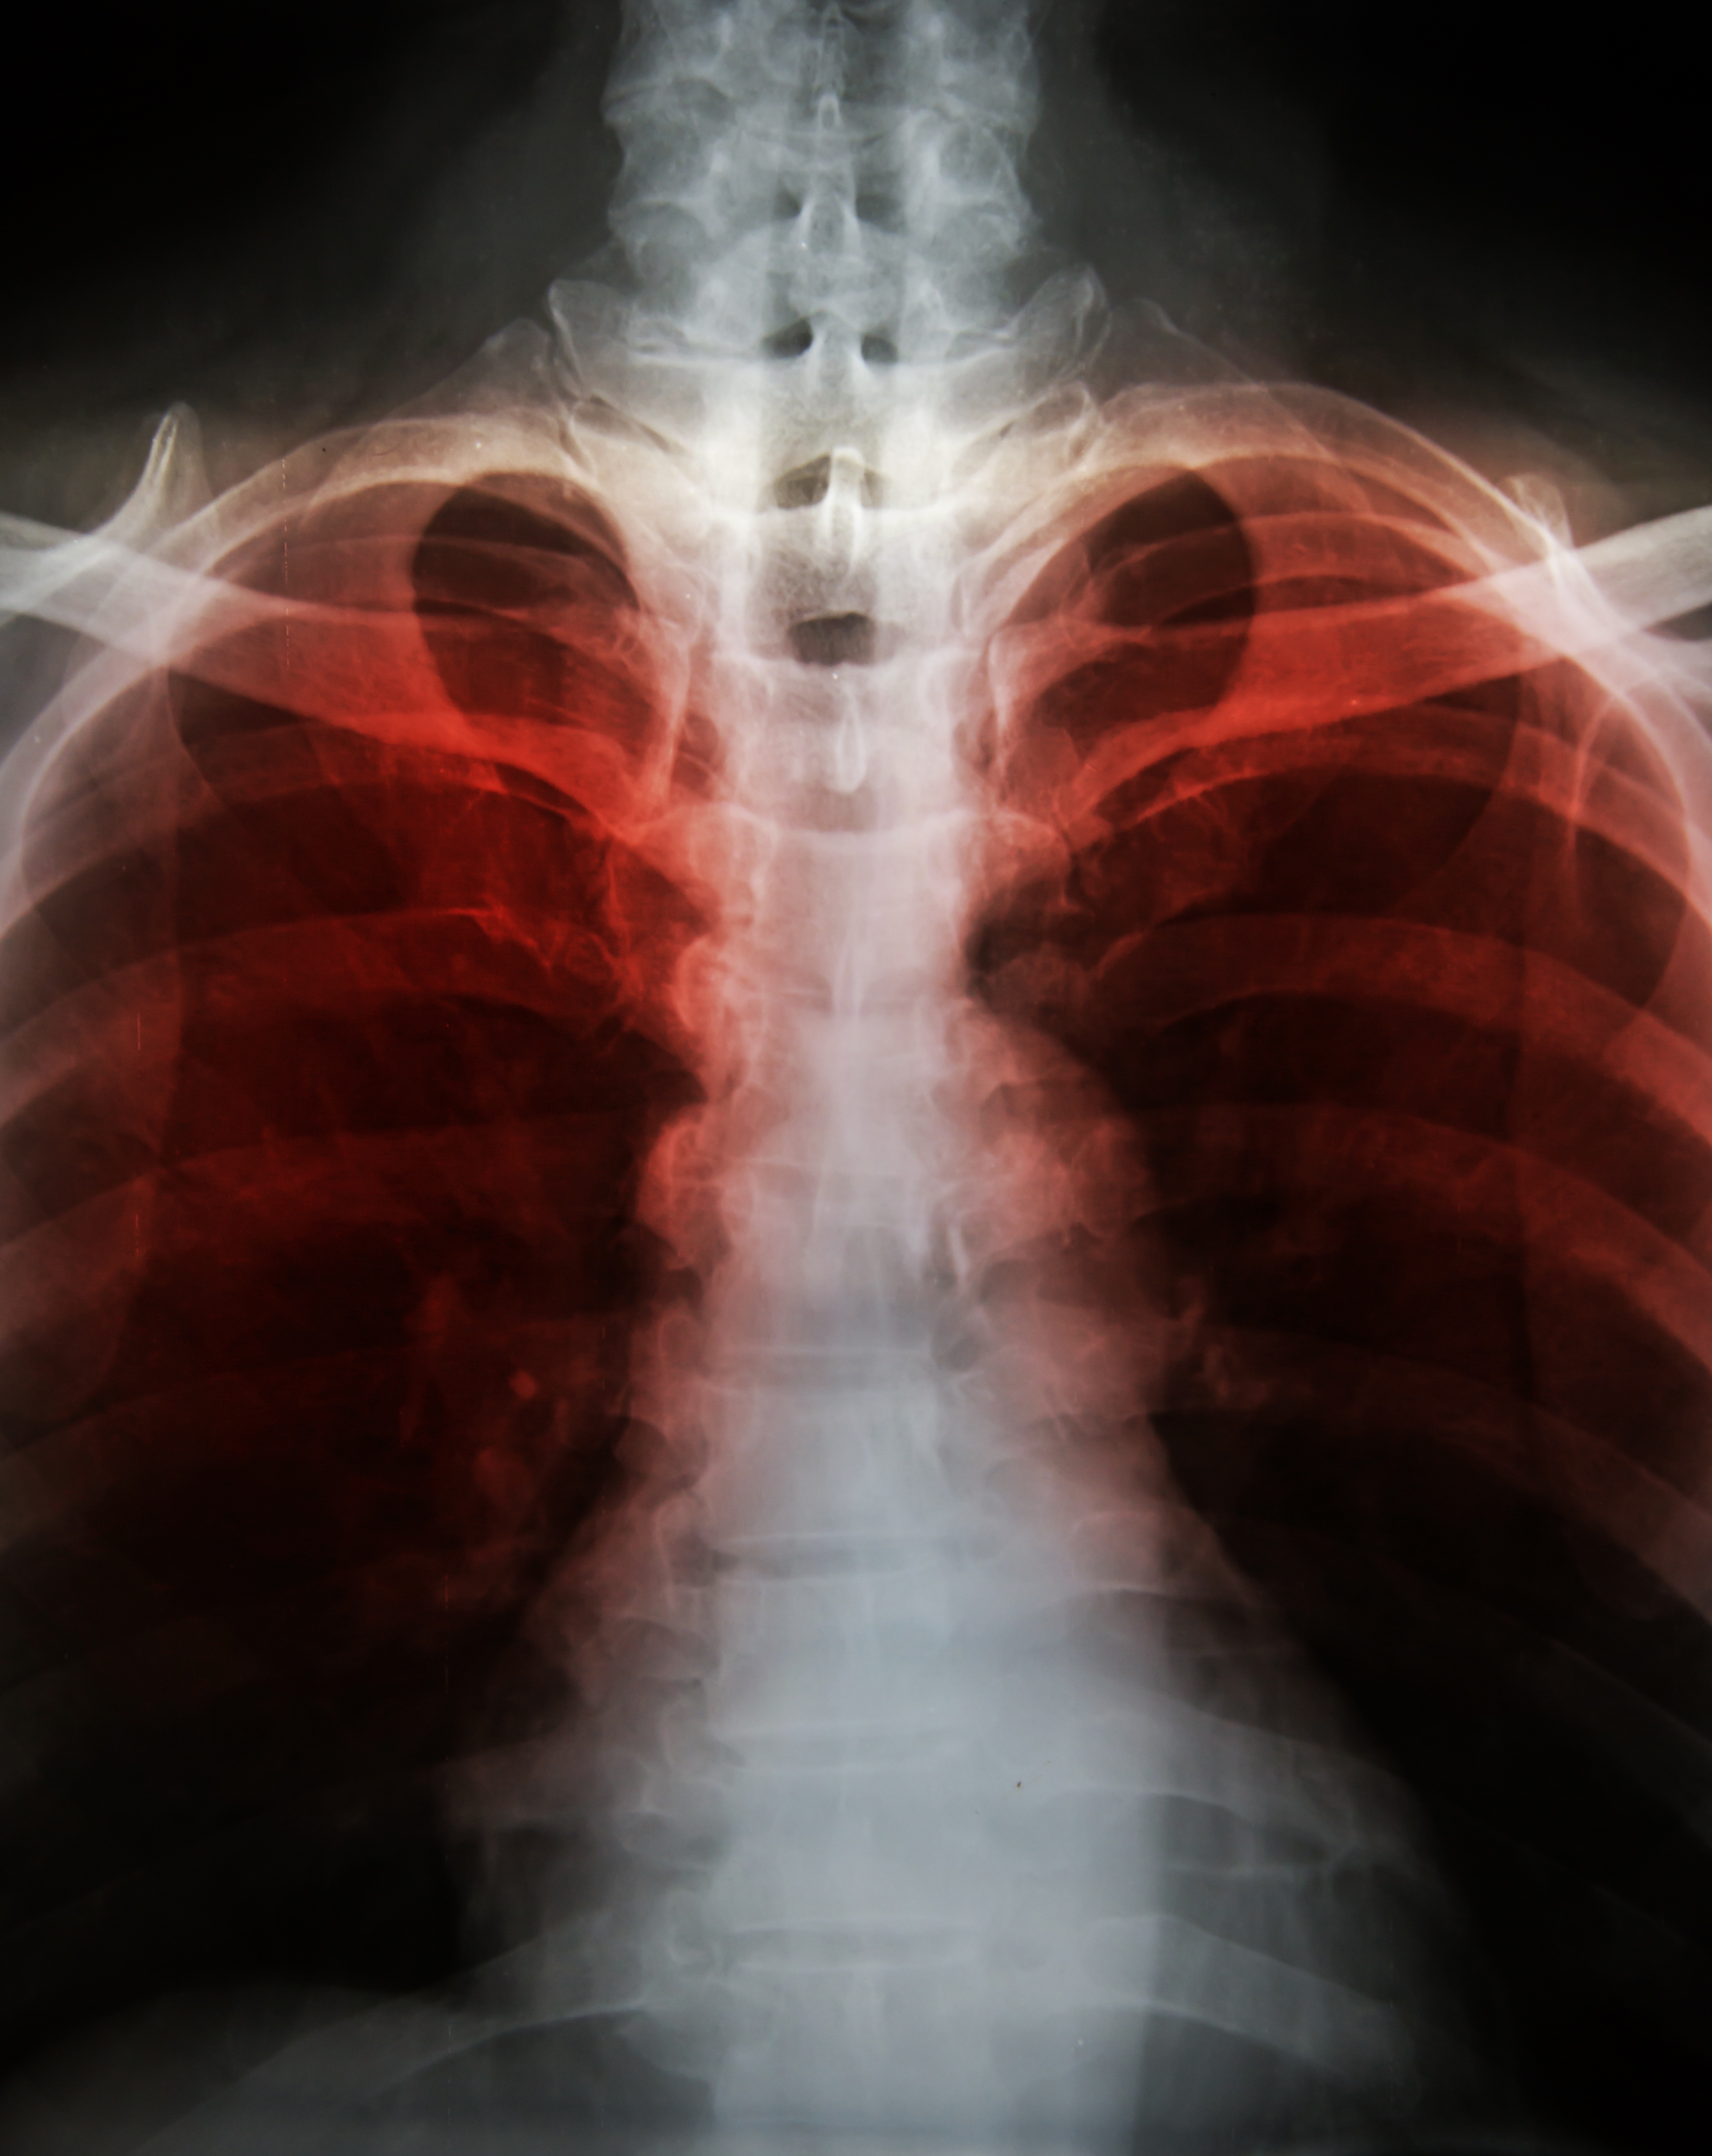

Differentiating Between COPD, Asthma, Emphysema and Bronchitis

Chronic obstructive pulmonary disease (COPD) is a chronic disease composed of multiple components, which can include asthma, emphysema and/or chronic bronchitis. To reach a diagnosis of COPD you must have two or more of these diseases as diagnosed by your pulmonary (lung) doctor. All of these are considered to be obstructive respiratory diseases. Obstructive lung diseases are categorized as such because they impair the ability of your body to breathe oxygen into the lungs and expire carbon dioxide out of the lungs. Since COPD is a combination of two or more diseases, your symptoms tend to be more severe than if you suffered from only one of the diseases. Let??s learn about each disease and find out how they all differ slightly from one another.